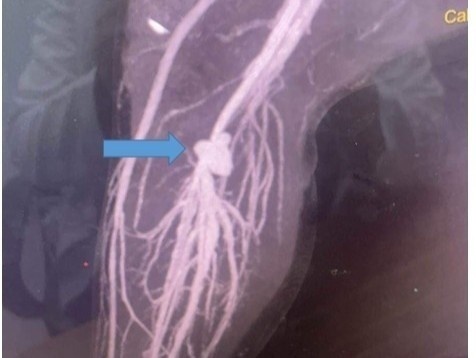

Trong lúc đùa giỡn, bé A.V.L. (11 tuổi) vô tình bị kéo nhọn đâm vào bắp đùi trái. Vết thương chảy máu, gây sưng đau nhiều ngày và dẫn đến phình mạch.